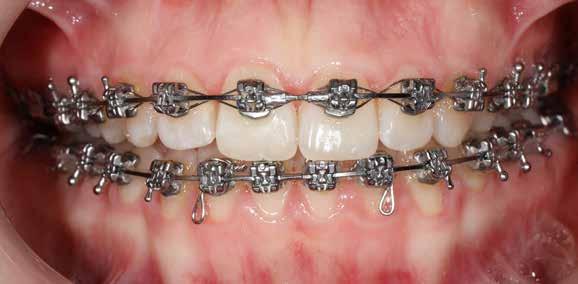

Ebben a cikkben egy 16 éves lánypáciens esetét szeretném bemutatni (1–7. képek)

A Pitts21-es fix készülékes kezelés során a harapásemelőket a felső nagyőrlő fogakra ragasztottuk, hogy a felső molárisok intrúziójával segítsék a harapás zárását (8. kép) Ún. keresztharapásos, majd később normál class 2-es gumihúzással (9–10. képek), továbbá az elülső fogakon alkalmazott ún. Rainbow harapás-záró gumihúzással (11. kép) korrigáltuk a jobb oldali teljes premolárisnyi distal-harapást, valamint az elülső nyitott harapást.

6 hónap után a nyitott harapás már nagyjából összezárásra került (12. kép)! A gumihordás a kezelés teljes hosszában folyamatos, éjjel-nappal, 22-24 órában az étkezések és az utánuk történő fogmosás kivételével.

A fix fogszabályozó készülék mindössze 16 hónapos kezelés után került eltávolításra! Páciensünk legnagyobb örömére állcsontműtét nélkül sikerült mind az arcesztétikai, mind a funkcionális rehabilitáció (13–18. képek)